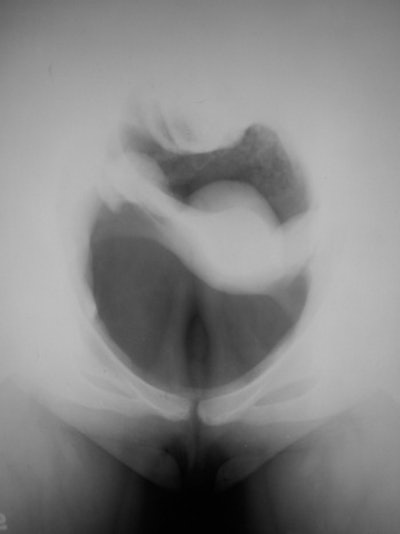

This retroperitoneal air study was performed in 1943 using a 10-cm needle.Diagnostic pneumoperitoneum/gynecography

In this technique, an abdominal radiograph is made following the induction of a pneumoperitoneum, and was developed by Eugen Weber from Kiev, Ukraine, in 1912. A specifically gynecological use was described by Otto Goetze from Halle, Germany, in 1918. The patient was placed head down and prone, and a pelvic radiograph was obtained with the pelvic viscera outlined with air. The uterus, bladder, and ovaries could be identified, and the bowel would fall out of the pelvis. Goetze said that he used the technique to diagnose pregnancy in the early months, infantilism, myomata, uterine and adnexal adhesions, pyosalpinx, and ovarian tumors. The patient illustrated below was examined in 1967 and the examination was normal. This was just before the introduction of ultrasound, which rendered the examination obsolete.